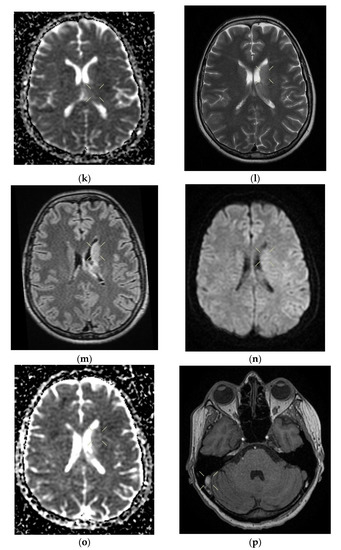

Figure 2. Cerebral native and contrast-enhanced MRI and angiography, and CT cerebral venography highlighting the sigmoid sinus and right lateral sinus thrombosis and the inferior sagittal sinus and right sinus thrombosis, associated with right temporal cortical and subcortical subacute hemorrhage, supratentorial recent subacute synchronous lacunar infarct, (cytotoxic and vasogenic) thalamic–lenticular–caudal edema, and supratentorial non-specific demyelinating lesions. Magnetic resonance imaging shows cortico-subcortical subacute hemorrhage in the right temporal lobe (a,b) T1 and T2 hyperintensities. (c) methemoglobin signal. (d) heterogeneous contrast enhancement. (e) supratentorial recent subacute lacunar infarction in a millimeter lesion in hypersignal FLAIR, restrictive in diffusion coefficient. (f,g) supratentorial recent subacute lacunar infarction located in the corpus callosum. (h,i,j,k) cytotoxic and vasogenic edema in diffuse T2 and FLAIR high signal and moderate restriction in diffusion coefficient in the left thalamus. (l,m,n,o) cytotoxic and vasogenic edema in left lenticular-caudate nucleus. (p) right sigmoid and lateral sinuses thrombosis—T1 and T2 hyperintense material, without contrast enhancement. The intravenous post-contrast and native cranio-cerebral MRI examination highlights are as follows: oval globular formations with a non-homogeneous central portion and a periphery with a methemoglobin signal, hyper-intense T1–T2, axial dimensions of 11/10 mm maximally and heterogeneous contrast outlet, along with right temporal cortical and subcortical conglomerates, with extended moderate perilesional oedema; FLAIR hyper-intense millimeter lesions, intense and homogeneous restriction in diffusion and no-contrast outlets in the semioval centers, in the corpus callosum and in the middle temporal gyrus; diffuse signal T2–FLAIR increased in the left and left lenticular–caudal thalamus, with minimum diffusion restriction and no detectable contrast outlets; a few T2–FLAIR hyper-signal millimeter outbreaks, with no diffusion restriction and no corresponding T1, located in the white matter in the periventricular hemisphere and bilateral frontal–parietal subcortical area; normal supra- and infratentorial pericerebral liquid spaces; a symmetric ventricular system, with normal dimensions; structures of the median line in normal position; orbits and orbital content without anomalies; and paranasal sinuses with normal development and pneumatization. Magnetic resonance (MR) cerebral arteriography and venography indicated the following: internal carotid arteries symmetrically disposed, with a normal trajectory and caliber; anterior cerebral arteries and normal average bilaterally detached from the internal carotid, with no areas of stenosis or circumscribed dilation, with a homogeneous intralumenal signal; vertebral arteries, basilar artery, upper cerebral arteries and communicating arteries with a normal trajectory and caliber; hyper-intense T1–T2 material, with a no-contrast outlet, which transversely occupied the sinuses and sigmoid on the right side; and a lesion with the same signal characteristics situated along the right sinus and extended towards the inferior sagittal sinus; the rest of the dural sinuses had no detectable lesions in the sequences observed.